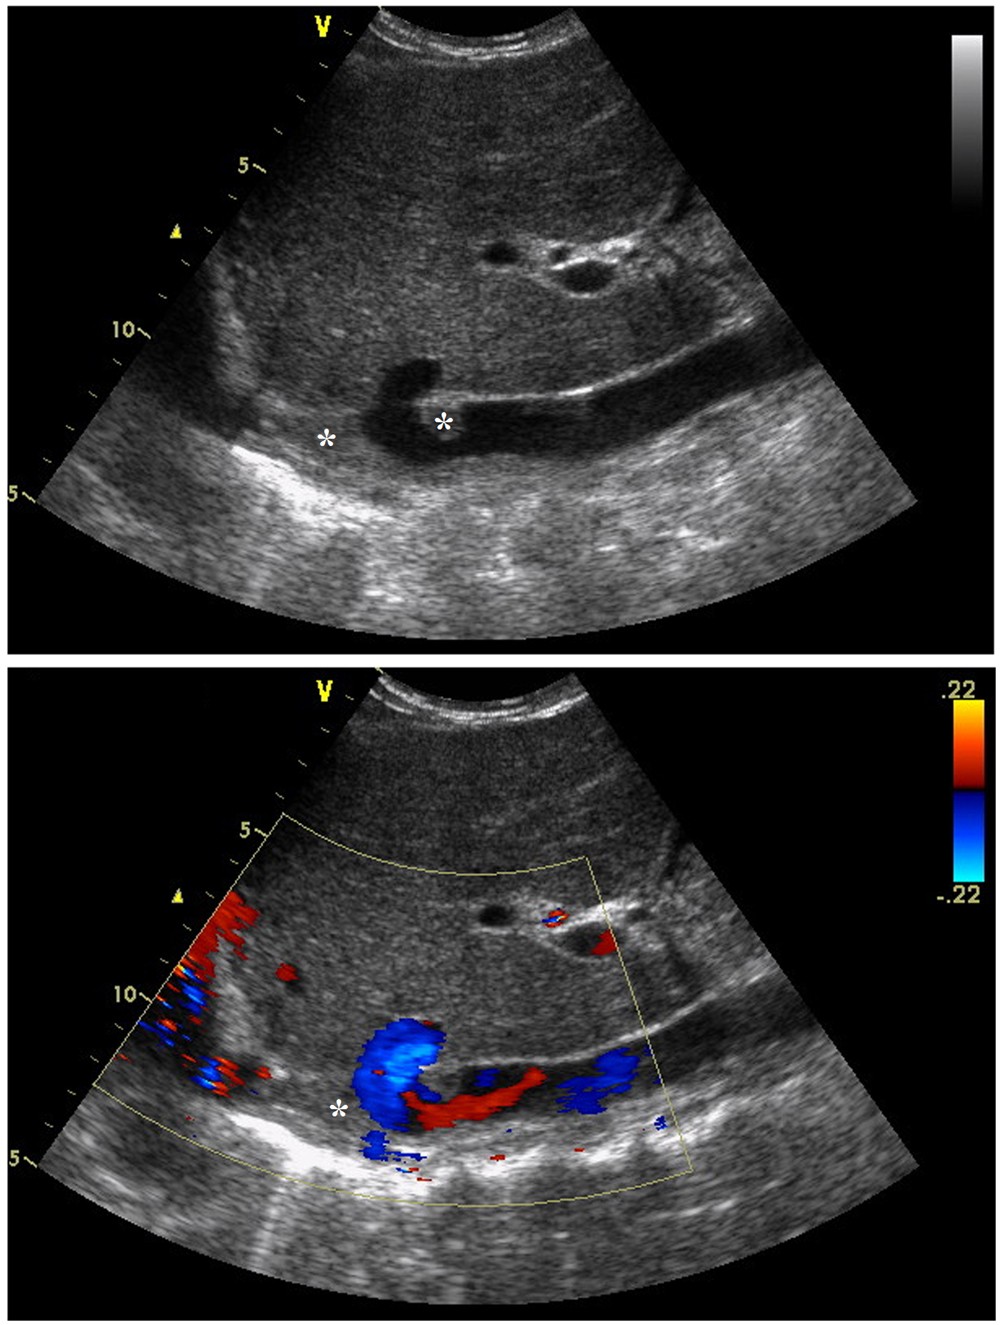

Figure 2

Preoperative color Doppler sonography. Segmental occlusion, thrombus and a small amount of blood flow echoes were shown in IVC. * indicated thrombus.